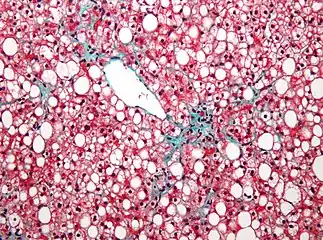

NAFLD comprises two histological categories: NAFL, and the more aggressive form NASH. The presence of at least 5% fatty liver is common to both NAFL and NASH, but the features of substantial lobular inflammation and hepatocyte injuries such as ballooning or Mallory hyaline only occur in NASH. The majority of NAFL cases show minimal or no inflammation.[3][5][7] Pericentral and perisinusoidal fibrosis occur more often in adult-onset NASH, whereas portal fibrosis is more common in children with the disorder. NASH represents a more advanced stage of NAFL and is associated with poor outcomes such as cardiovascular events, cirrhosis, or hepatocellular carcinoma. ICD-11 does not use the term NAFL as it was deemed confusing with the family of disorders NAFLD. The preferred descriptions are instead: MAFLD without NASH or simple steatosis and "NASH". Also, the modifier with or without fibrosis or cirrhosis completes the diagnostic description.[3][7]

| score | ||||

|---|---|---|---|---|

| 0 | 1 | 2 | 3 | |

| Steatosis | <5% | 5- 33% | >33- 66% | >66% |

| Lobular inflammation | None | <2 foci | 2- 4 foci | >4 foci |

| Hepatocyte ballooning |

None | Few | Many/prominent | |

The AASLD and ICD-11 consider that clinically useful pathology reporting distinguishes "between NAFL (steatosis), NAFL with inflammation and NASH (steatosis with lobular and portal inflammation and hepatocellular ballooning)" with the presence or absence of fibrosis being described and optionally comment on severity.[5][7] The EASL recommends the Fatty Liver Inhibition of Progression (FLIP) algorithm to grade the ballooning and classify MAFLD-associated liver injury, and the use of the NAFLD Activity Score (NAS) to grade the severity of NASH rather than for its diagnosis. They also consider the steatosis, activity, and fibrosis (SAF) score to be an accurate and reproducible scoring system.[16] The AASLD recommends the use of the NAS scoring system with or without the SAF score if deemed appropriate.[5] The Asia-Pacific Working Group on MAFLD disadvises the use of NAS, as it is considered uninformative for NAFLD and inappropriate to diagnose NASH.[14]